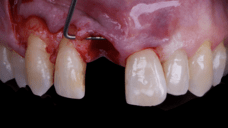

The surgical protocol began with the atraumatic extraction of tooth 1.1 to preserve as much of the alveolar socket as possible. Immediately following extraction, an N1 implant was placed into the socket using a guided surgical approach to ensure ideal three-dimensional positioning. The “one abutment one time” technique was applied to minimize soft tissue manipulation during the healing phase, which is particularly important in esthetic areas.

Given the significant buccal defect, guided bone regeneration (GBR) was performed simultaneously. A mixture of autologous bone and creos™ xenogain™ was applied to the defect and covered with a resorbable creos™ membrane to restore ridge width and support the buccal contour. In addition, a connective tissue graft was harvested and placed in the vestibular region to increase the thickness of keratinized mucosa. This combined approach addressed both hard and soft tissue deficiencies, providing the biological foundation for a stable and esthetic outcome.

On the same day as the surgery, an immediate-load provisional crown was delivered. This restoration was fabricated in acrylic resin and screw-retained on the implant, following the “one abutment one time” principle. The provisional crown was carefully adjusted to avoid occlusal loading while supporting the peri-implant soft tissue architecture during the healing phase.